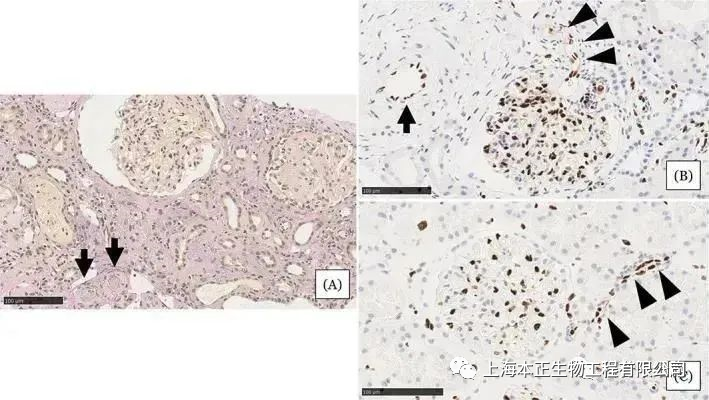

Semeclo证实干细胞可能通过免疫反应调节和增强抗纤维化分子表达改善肾功能和减轻肾纤维化。Villanueva,Lee,Wu等证实使用MSC可以改善肾功能,同时减轻肾脏损伤,减少胶原蛋白在肾脏沉积、抑制模型动物肾纤维化。朱凤阁等使用C57/BL6小鼠建立单侧输尿管梗阻(UUO)小鼠模型,术后立即从尾静脉靶向使用间充质干细胞(MSCs),发现MSCs对肾小管间质纤维化的保护作用,部分归因于其促进肾脏内三级淋巴样器官的新生。